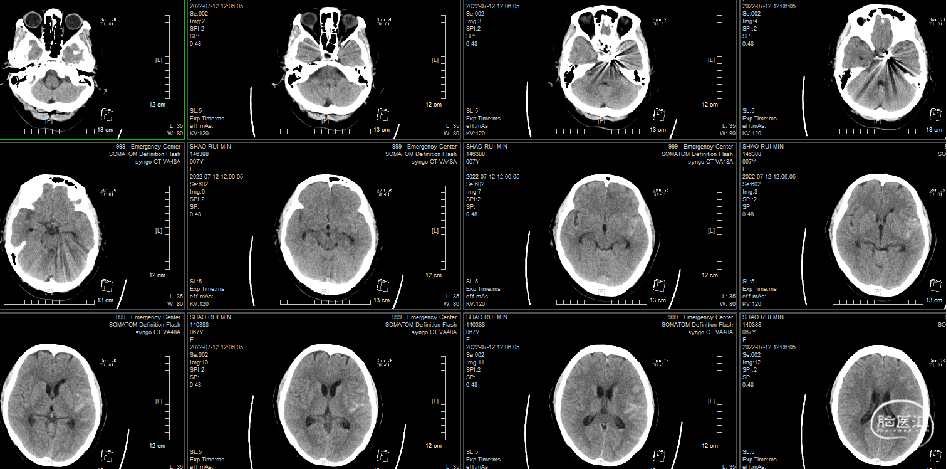

头颅CT(平扫)、胸部CT(平扫)第一次:

1、自发蛛网膜下腔出血,建议CTA检查。

2、双肺陈旧病变,双肺感染,双侧胸膜肥厚。

急诊头颅CT:自发蛛网膜下腔出血。

2022-7-12复查(术后第7天):头颅血管术后改变,蛛网膜下腔出血、脑室积血有吸收。病人头痛明显,腰穿压力330,给予甘露醇250ml Q12h

2022-7-14复查头颅CT+CTA:蛛网膜下腔积血明显减少。